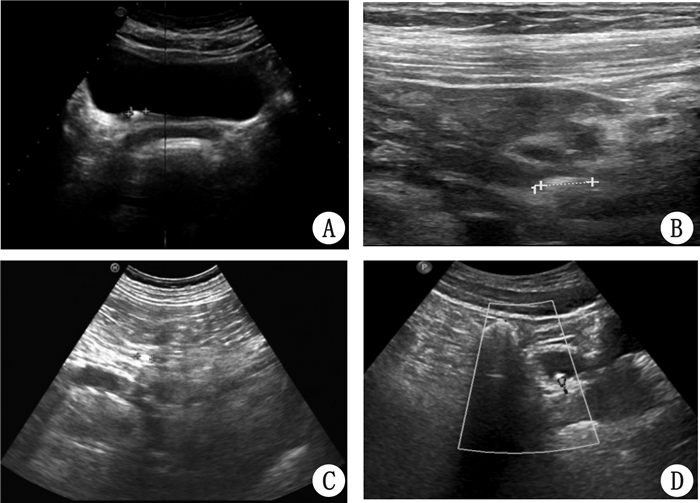

2 结果本组漏诊的18例患者,上段结石5例,中段3例,下段10例(经二次超声、静脉肾盂造影、逆行性肾盂造影或输尿管镜证实),肾脏均无明显积水,结石近端输尿管无明显扩张或扩张内径约3 mm左右,从而忽略了对输尿管的追踪扫查。漏诊的结石长径为0.54~1.40 cm,平均约0.73 cm。8例患者膀胱充盈较差,首次超声输尿管末端无法显示,二次超声时膀胱充盈较好,检出结石位于输尿管膀胱壁内段或靠近膀胱处(图 1A)。1例输尿管上段结石经二次浅表超声检出(图 1B);3例输尿管上段结石、1例输尿管中段结石由资深的超声医师二次超声检出(图 1C);其余1例输尿管上段结石、2例输尿管中段结石和2例输尿管下段结石经二次以上超声均未检出,后经静脉肾盂造影、逆行性肾盂造影和输尿管镜证实。

| A:输尿管壁内段结石;B:高频超声探及上段输尿管结石;C:输尿管中段结石;D:输尿管结石的彩色彗尾征 图 1 患者输尿管超声影像 |

为了提高超声诊断的准确率,现将多年来在输尿管结石诊断过程中的经验、体会总结如下:① 检查时遵循先两头后中间的原则,输尿管结石主要位于输尿管下段,次之上段,下段结石的发病率最低[16]。② 可根据患者疼痛部位不同有重点的进行探查,输尿管上段梗阻时,可出现肾绞痛,并沿输尿管行径放射至同侧睾丸或阴唇和大腿内侧;输尿管中段梗阻时,疼痛放射至中下腹部;当结石位于输尿管下段时,常伴有膀胱刺激征及向尿道和阴茎头部放射。③ 多种频率探头联合应用,肥胖患者用低频探头,瘦弱患者和儿童患者可使用高频探头,膀胱未充盈患者在条件允许的情况下可使用腔内探头。④ 当结石和肠内容物无法鉴别时,应用结石的彩色多普勒特异性征象“彩色慧尾征”加以鉴别(图 1D)。